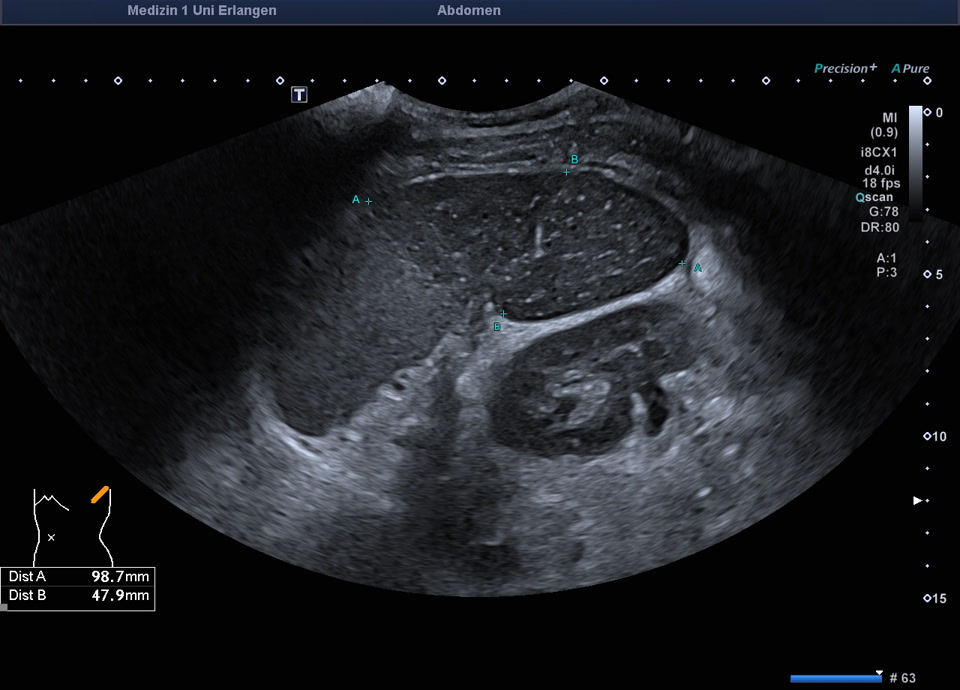

Splenic infarction

• Splenic infarction after coiling of splenic artery

Milzinfarkt am Oberpol bei Z. n. Coiling der A. splenica (Indikation zum Coiling: Blutung aus der A. splenica in eine Pankreaspseudozyste), siehe auch nächstes Video

Milzinfarkt am Oberpol bei Z.n. Coiling der A. splenica (Indikation zum Coiling: Blutung aus der A. splenica in eine Pankreaspseudozyste)